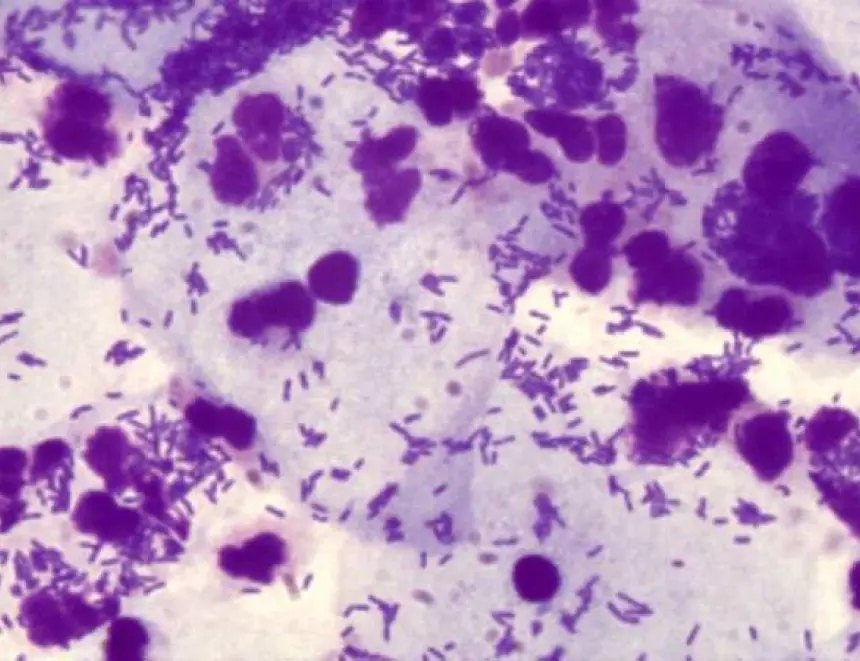

پیتھوجینک مائکروجنزم اور بیکٹیریا پروسٹیٹ میں بڑھ جاتے ہیں۔ بیکٹیریل پروسٹیٹائٹس تیار ہوتا ہے۔ غدود کے ؤتکوں میں ناقابل واپسی تبدیلیاں واقع ہوتی ہیں۔ یہ پروسٹیٹ اڈینوما کی طرف جاتا ہے - ایک سومی تشکیل (پیتھوجین کی موجودگی کی وجہ سے، خلیات ناکافی طور پر تقسیم ہونے لگتے ہیں)۔

اڈینوما کیا ہے؟ یہ بہت خطرناک حالت ہے۔ یہ اکثر اونکولوجی کی ترقی اور ایک مہلک نتیجہ کی طرف جاتا ہے.

بدقسمتی سے، پروسٹیٹ ٹشو بہت نازک ہے، اور اس وجہ سے مندرجہ بالا تمام تیزی سے تیار ہوتے ہیں. پہلی علامات سے لے کر ناقابل واپسی حالت تک، صرف چند سال گزر سکتے ہیں۔